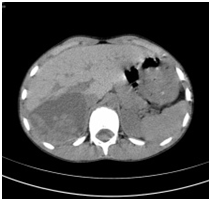

Figure 2 Vessels with diameter less than 2mm were sealed using humid bipolar coagulation. The other vessels were traditionally dissected and ligated.

Ten consecutive patients with liver echinococcal cysts that didn’t meet criteria for PAIR treatment (M: 4, F: 6), with a mean age of 31, 3± 14 years (range 8-54) were prospectively enrolled and operated in the Department of Surgery of Peja Hospital (Kosovo) from Feb 2006 until Apr 2010. Preoperative evaluation of the patients included blood tests (complete blood count, liver function tests and anti-echinococcus antibody testing) abdominal US and computerized tomography (CT). Five patients had single and 5 patients multiple cysts for a total number of 16 cysts. Three patients had previous surgery for hydatidosis: 1 patient had partial cystectomy 3 years before and come for recurrence, another patient with cysto biliary fistula underwent an unclear attempt to remove the cyst and cholecystectomy 3 months before (Figure 1) and another patient was previously operated for lung echinococcosis. One patient underwent PAIR 1 year before operation. According to the relationship with the main vascular and biliary structures, cysts were classified as peripheral (n= 4, 25%) or central (n= 12, 75%), when they had very close relationship with the main vessels. CT scan was considered mandatory for an adequate operative plan. RMN and ERCP were not available in the country during the study period. An intraoperative cholangiogram was obtained only in case of clinical history or laboratory tests alteration suggestive for bile duct obstruction. All patients were treated with Albendazole before surgery and in the perioperative period. Treatment was stopped immediately after surgery if during the operation the cysts were not opened. To prevent accidental spillage into the abdomen, the operative field was protected with gauzes soaked by hypertonic saline solution. Parenchymal transection was performed by clamp-crush technique. During the operation, afferent blood vessels and biliary ducts were ligated between the pericyst and the normal liver. Vessels less than 2mm in diameter were sealed using humid bipolar coagulation (Figure 2). No other devices were available to transect the liver, or glues to treat the cut surface.

Sixteen cysts were excised in 10 patients. Nine patients underwent radical surgery; 5 had multiple cysts and were submitted to hepatic resection (1 right and 2 left hepatectomy) or multiple total pericystectomy with closed cyst. Four patients with single cyst underwent total pericystectomy with closed cyst. Only 1 patient underwent a non-radical operation and a subtotal pericystectomy was performed. In this case the cyst was opened and a small piece of the pericystium was left in place close to the right branch of the portal vein and the bile duct. A cysto-biliary fistula with the right posterior bile duct was sutured after washing of the biliary tree. Only in one case intermittent Pringle maneuver was used to control bleeding. In the other cases the inflow was controlled by selective clamping, if necessary. In 2 cases previous clamping at the origin of the right hepatic vein was performed before dissection of the vein from the pericystium. Intraoperative ultrasound was necessary only in one case of subtotal pericystectomy. It was always possible to dissect the main veins from the pericystic wall (Figure 2-4), while it was necessary to sacrifice the structures of the portal triad when they were fused in the pericyst. Mean operative time was 236 min. All patients were extubated at the end of the procedure. Mean postoperative stay was 5.2± 2,52 days (range 3-10), with no mortality and only 1 low output biliary fistula in the case of subtotal pericystectomy that healed after 9 days. Postoperative stay was longer for children because they lived far from the hospital. Mean follow up is higher than 3 years and until now no recurrence were observed (Figure 5).